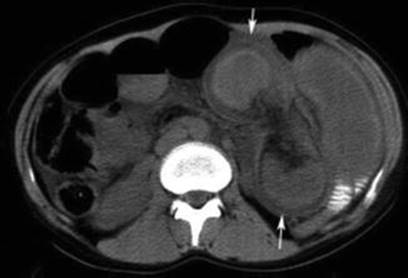

As with any case of suspected ileus or obstruction, electrolyte levels are an essential investigation, and in the 48 cases of Ogilvie’s syndrome reported by Jetmore et al., 83 % demonstrated at least one electrolyte disturbance with hypocalcaemia being the most common [36]. Plain abdominal radiographs are generally diagnostic with significant colonic distention (cecal diameter ≥7 cm), with minimal or no distention of the small intestine [38, 43–46]. Abdominal radiography is a standard first-line investigation, and Keswani et al. reported that a cecal diameter ≥9 cm (Fig. 7.1) is the “only definitive sign of imminent perforation” [42]. Serial plain abdominal X-ray is important for the definition of the progression along with WBC and CRP. CT can be used in doubtful cases to exclude other etiologies of obstruction (Fig. 7.2).

Fig. 7.1

Plain supine abdominal radiograph showing widespread colonic dilatation with no free air [47]